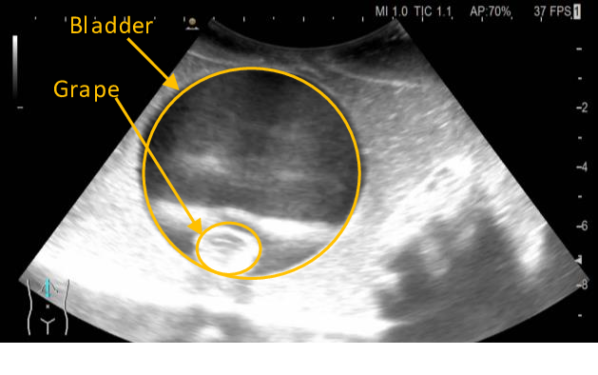

III-C Ultrasound Scan Experiment

The ultrasound scan experiment evaluates the ability of the system to perform a remote diagnostic test, which requires the design of an end-effector for holding the ultrasound probe (Fig. 4.c). However, the available ultrasound scan does not allow remote control, so the experimental setup has been modified. This experiment is performed in the line of sight teleoperation. However, the phantom was placed above the operator’s line of sight to hinder the perception and promote the use of the video feedback from the ultrasound scan. We use a phantom made of commercial food gelatin mixed with psyllium husk to enhance the contrast. We have three layers of gelatin with different water components; the first has the recommended water to gelatin ratio. In the second layer, the amount of water is halved, and on the top layer, the water is reduced to one third. Multiple props are suspended in the mix. There are bladders made of water balloons with grape inside to mimic masses, and some fruit (grapes) is also distributed outside the bladder directly in the gelatine. It is worth noting that we have used a high-frequency probe that is not ideal for the quality of the image. However, it does not make any difference in evaluating the physical interaction stability and dexterity, which are objectives for this experiment.

Fig. 11 shows the evolution of the interaction forces, the user input () and the stiffness of the replica arm, showing how the proposed method can dynamically adjust its stiffness to interact with the nonlinear environmental dynamics. The video also allows us better to appreciate how, once the contact is made with the phantom, the exploration can be driven mainly relying on the ultrasound monitor shown in 12. The main limitation in this experiment was that the available ultrasound did not allow remotely adjusting the image; thus, it requires being physically close to the patient.

The ultrasound scan experiment showcased that it is possible to accurately control the probe for conducting a scan. The feedback from the scan monitor is sufficient to conduct the test once the contact is made with the tissue; however, the 3D visual perception is essential to make contact with the desired anatomical district, which was possible thanks to the line of sight set-up used for this experiment. The main limitation to the deployment of this technology is the lack of remote control for the ultrasound scan, which limits the distance of the operator from the patient to the length of the probe. Nevertheless, this application is currently the closest to eventual clinical testing among the evaluated scenarios.